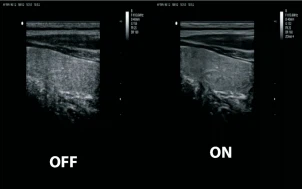

Frequency Composite Imaging

Частотный компаундинг обеспечивает повышение качества визуализации за счет объединения в одно изображение нескольких изображений, полученных на разных частотах излучения.

Pulse Inverse Harmonic Imaging (PIHI)

Тканевая инверсная (пульсинверсная) гармоника - технология выделения гармонической составляющей колебаний внутренних органов, вызванных прохождением сквозь тело базового и инверсного ультразвуковых импульсов. Полезным считается сигнал, полученный в результате сложения базовой и инверсной составляющих отраженного сигнала. Технология снижает искажения, создаваемые основной волной, и значительно улучшает отношение сигнал/шум.

ZClear

Tехнология отслеживает специфические сигналы от краев ткани в режиме реального времени для улучшения границы и контура, одновременно отслеживая каждый пиксель для оптимизации сигнала от ткани. Эффективно устраняет шум и идеально формирует изображения границ ткани и двумерную визуализацию с улучшенным контрастом.